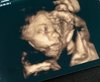

Zobacz załącznik 871739 Cześć , ja dziś rano miałam wizytę emergency u swojego giną, bo od godz 7 miałam mocne, regularne skurcze..... okazało się za fałszywy alarm, Polka zmieniła ułożenie o 180 stopni i to pewnie pobudziło macice do skurczy... ogólnie wszystko ok , dostałam na wszelki wypadek luteinę do pobrania ,szyjka długa 6 cm, Pola rośnie , łożysko ok ... więcej odpoczynku w domu i lecimy dalej![]()